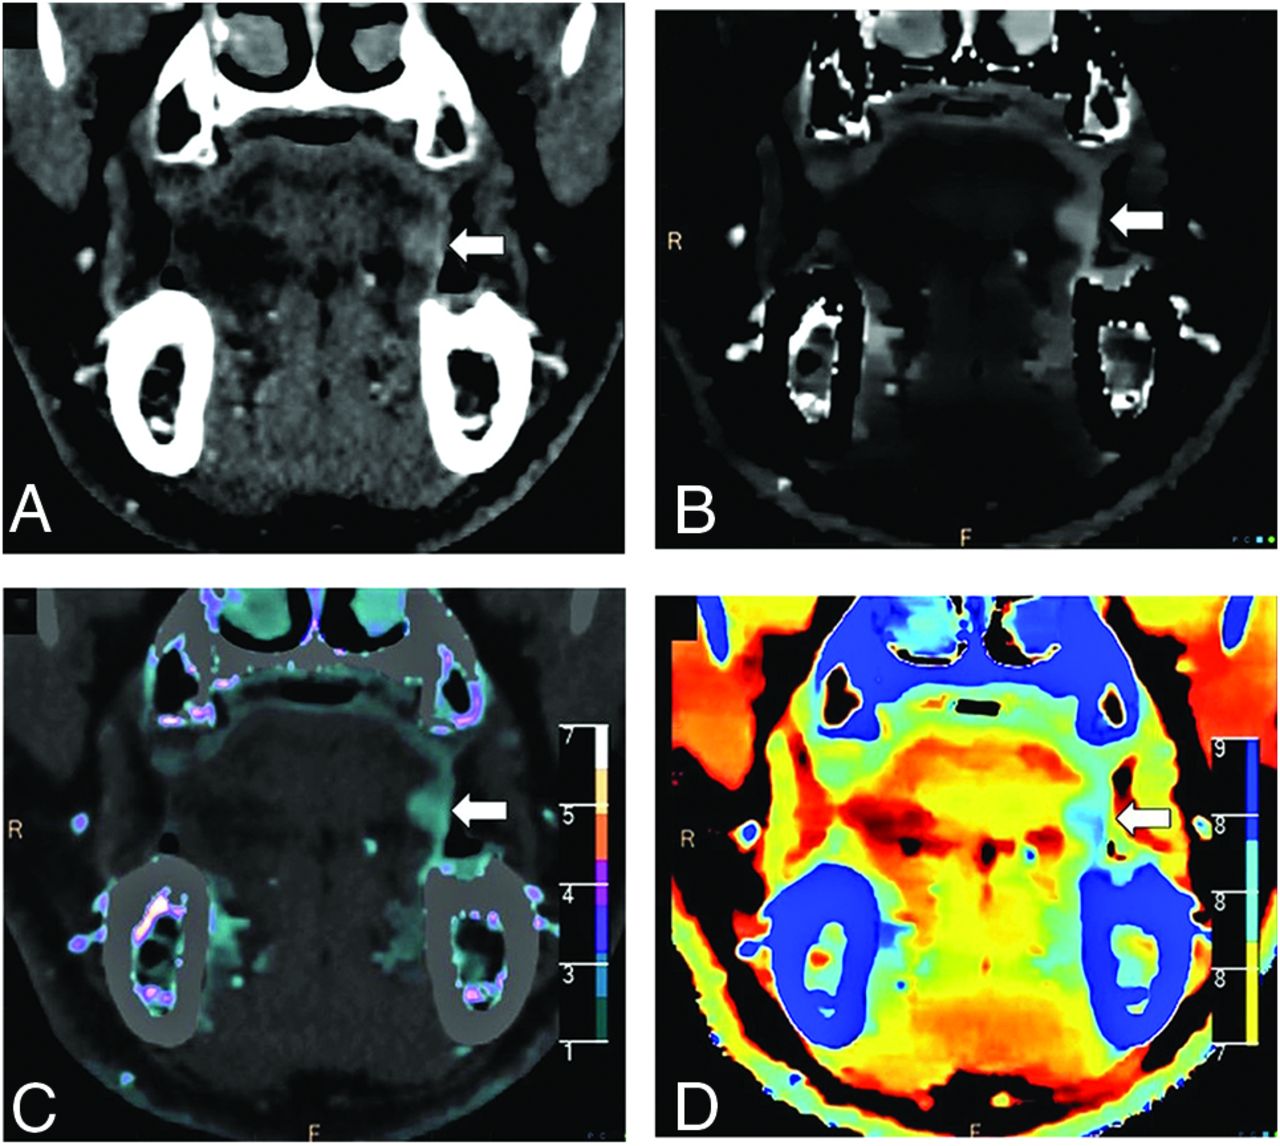

A 63-year-old man with left buccal and alveolar mucosa squamous cell carcinoma (arrows) seen on the conventional images in soft-tissue (A) and bone (B) window settings. Iodine density (B), color iodine density overlay (C), and Z-effective (D) images reveal right mandibular bone invasion with increased iodine density in the medullary cavity of the left hemimandible (arrowhead). T1-weighted MR imaging (E) and post-gadolinium-enhanced T1 fat-saturated (F) image confirm bone marrow infiltration. The patient was upstaged from T3 to T4a.